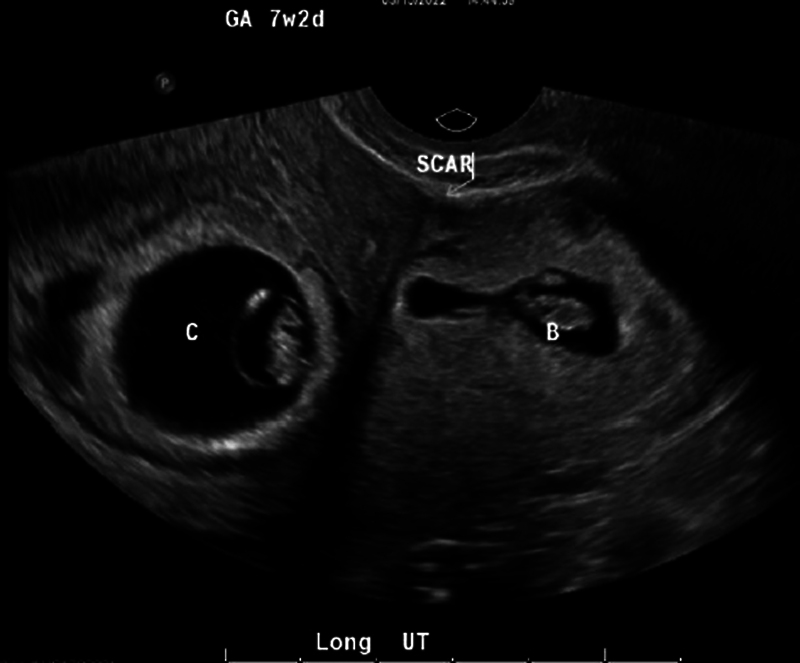

异位三胎妊娠、剖宫产瘢痕异位妊娠和子宫消融术后妊娠都是罕见的情况,会导致自然流产、宫内胎儿死亡、早产、胎盘异常和子宫破裂等重大疾病。一名 30 多岁的女性(G6P4014)曾做过子宫消融术,出现月经推迟和阴道点滴出血,造影显示两次宫内妊娠(其中一次有胎心活动),一次在剖宫产疤痕处活胎。医生对患者进行了广泛的咨询,让她了解自己和胎儿面临的风险,并讨论了各种治疗方案,包括预产期管理和终止妊娠。患者接受了不复杂的扩张刮宫术和双侧输卵管切除术,术后当天就出院回家,情况稳定。本病例强调了合并症的潜在复合效应,这些合并症会给咨询和管理带来困难。要点 接受子宫内膜消融术的患者应经过仔细挑选,并在高效避孕方面进行广泛咨询。许多情况都会对产妇的健康造成严重威胁,因此有必要讨论终止妊娠。

Heterotopic triplet pregnancy, cesarean scar ectopic pregnancy, and pregnancy following uterine ablation are all rare events that confer significant morbidity including spontaneous abortion, intrauterine fetal demise, preterm labor, abnormal placentation, and uterine rupture. A woman in her 30s, G6P4014, with a history of uterine ablation presented with delayed menses and vaginal spotting with imaging showing two intrauterine pregnancies (one with cardiac activity) and one live pregnancy at the cesarean scar. The patient was extensively counseled on risk to her and to the pregnancies; treatment options were discussed including expectant management and termination of pregnancy. The patient underwent an uncomplicated dilation and curettage with bilateral salpingectomy and was discharged home the day of the procedure in stable condition. This case highlights the potential compound effect of comorbid conditions that can pose difficulty in counseling and management. Key Points Patients undergoing endometrial ablation should be carefully selected and counseled extensively on highly effective contraception.Suspected cesarean scar pregnancies should be carefully evaluated early in gestation. Management should include thorough counseling and may be indivisualized.Many conditions pose a significant threat to maternal health and warrant a discussion of termination, which should be widely availaible and safe for all who need and/or desire it.